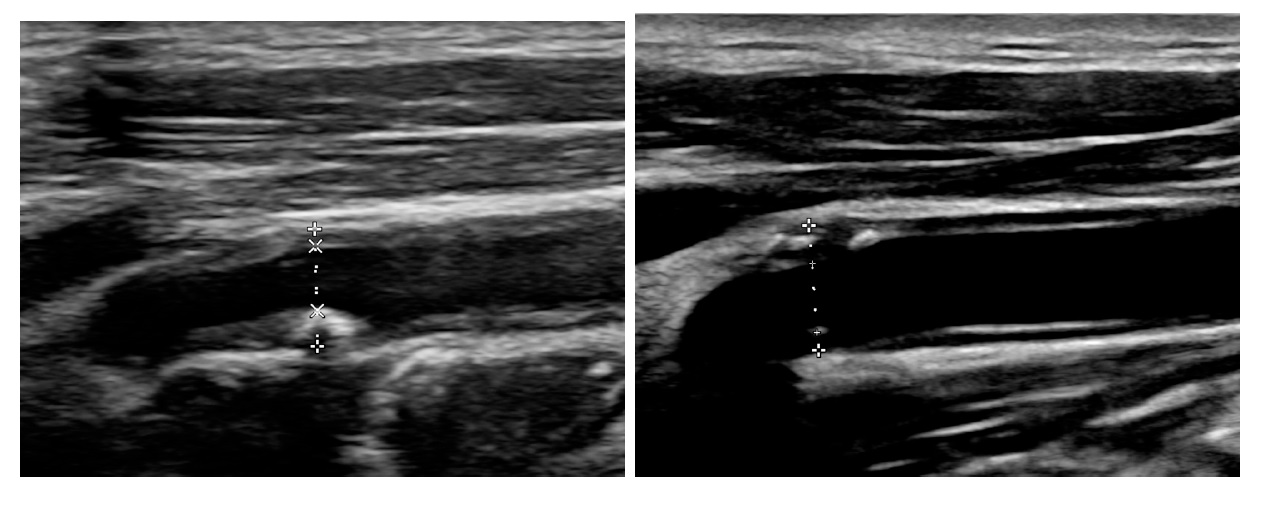

圖說:左圖為病人於 2022 年進行的頸動脈超音波檢查,可見血管內有明顯斑塊與狹窄,顯示動脈粥樣硬化程度嚴重。右圖為 2025 年追蹤檢查結果,血管斑塊明顯縮小、血流通暢且彈性改善,顯示經高強度降血脂藥(他汀類藥物)治療後,血管狀況顯著好轉/臺大醫院新竹分院提供

這名男性病人2017年因舌癌接受放射線治療,長期受到口乾與高血壓等問題困擾。2021年影像檢查顯示其右側頸內動脈已有明顯斑塊及約50%的血管狹窄,屬於高風險族群。自2018年起在心血管中心團隊照護下,病人每天規律服用降血脂藥(他汀類藥物,Statin),並持續追蹤血管變化。最新的2025年追蹤影像顯示,頸動脈斑塊體積明顯減少、血管壁恢復光滑,血流更為順暢,顯示治療獲得良好成效。

新竹臺大分院心血管中心張恕桓醫師指出,這位病人曾接受放射線治療,血管內皮容易受損,更容易形成粥樣硬化斑塊。長期使用高強度降血脂藥物能有效降低壞膽固醇(LDL)濃度,穩定甚至縮小斑塊體積。這次影像比對中,於2022年雖仍見顯著斑塊,但持續使用降血脂藥物之下,2025年已有明顯改善,其實積極控制血脂肪為臨床上醫師常常進行的決策處方,也符合國際治療指引,只是常常沒有機會讓一般民眾看到其治療成果。